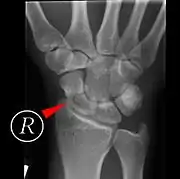

Переломи човноподібної кістки погано піддаються рентгенівській діагностиці, тому необхідна повторна рентгенограма по спливанні певного часу, або КТ чи МРТ[8].